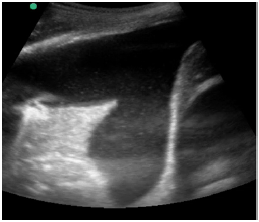

Um paciente de 72 anos de idade foi para a Unidade de Terapia Intensiva (UTI). Institucionalizado, com duas internações nos últimos seis meses por conta de sepse de foco urinário. Na admissão, realizou ultrassonografia abdominal com o achado demonstrado na imagem apresentada. Os exames laboratoriais mostraram ureia = 230, creatina = 10 e potássio = 7,5.

A cobertura antibiótica mais adequada para esse caso seria

Uma sonda vesical de demora foi alocada no paciente. A coloração esverdeada da urina desse paciente sugere qual agente etiológico?

O que tem demonstrado nessa ultrassonografia beira-leito e qual a conduta a ser tomada?